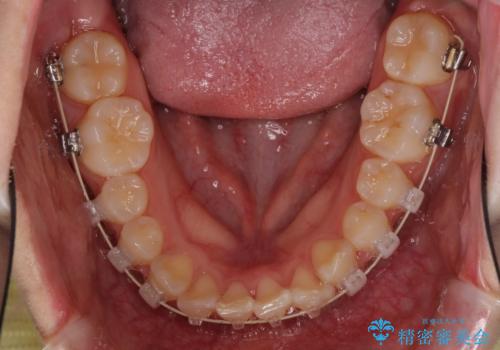

- 矯正装置

- インビザライン・審美装置

インビザライン単体で治療を行うには叢生が強いと判断されたため、事前にワイヤー装置で抜歯矯正を行い、ある程度改善してからインビザラインにて仕上げていくこととしました。